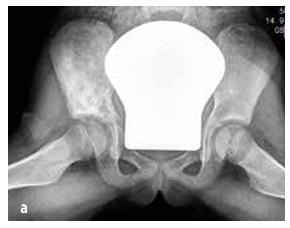

Код деце најчешћи типови су остеосарком (55%, видети Слику 5) и Јуин сарком (35%, видети Слику 6), док је хондросарком изузетно редак. У ову групу такође спадају саркоми меких ткива (рабдомиосарком и нерабдомиосаркоми), мезенхимални ћелијски тумори, екстраскелетни Евингов сарком, синовијални сарком, фибросарком и ембрионални сарком.

Слика 6

Јуингов сарком који погађа карлични скелет